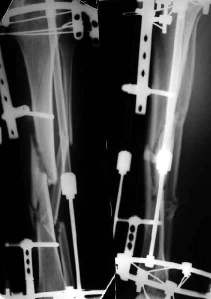

Неправильно сросшийся перелом голени

Уважаемые коллеги! На консультации больной предъявляет жалобы на хромоту (укорочение - 2см), боль в месте перелома при нагрузке (спортсмен).

Семь месяцев назад получил закрытый перелом, лечился консервативно в одной из больниц города. Как-бы кто лечил? Сам склоняюсь к LCP с костной пластикой.

При невозможности или чрезмерной травматичности одномоментного восстановления длины можно пойти двухэтапно (аппарат, потом гвоздь). Похожий пример см. тут. Прошло уже года полтора после остеосинтеза. Может, коллега Зырянов покажет годичный результат, если есть?

Отправитель: Сергей Зырянов 16 Декабрь 2005, 08:20

Александр Николаевич, к сожалению больной не является на контрольные осмотры. Я последний раз видел больного, когда прошло 7 месяцев после операции БОС. У него все хорошо. Каких либо жалоб и ограничений в нагрузке нет. Высылаю снимки до операции и последние снимки.